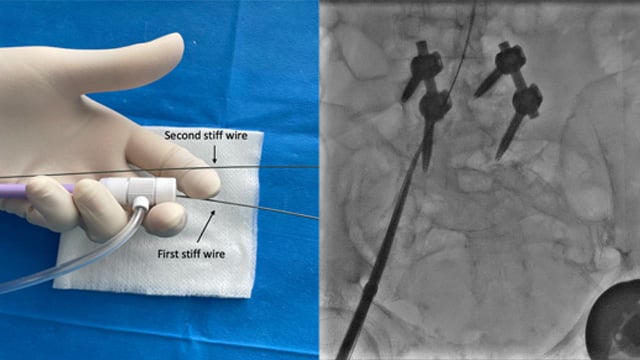

Distal Radial Access

Distal radial access is transforming vascular interventions. Explore this step-by-step My Toolkit guide to overcome technical challenges, preserve radial arteries, and deliver safer, more comfortable procedures.